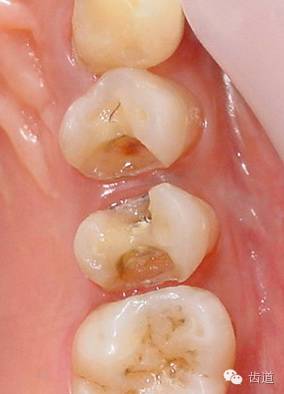

1、上頜前磨牙銀汞充填后食物嵌塞

2、去除銀汞充填物并作嵌體牙體預(yù)備

3、樹脂暫時(shí)嵌體覆蓋窩洞

4、瓷嵌體制作

5、瓷嵌體粘結(jié)